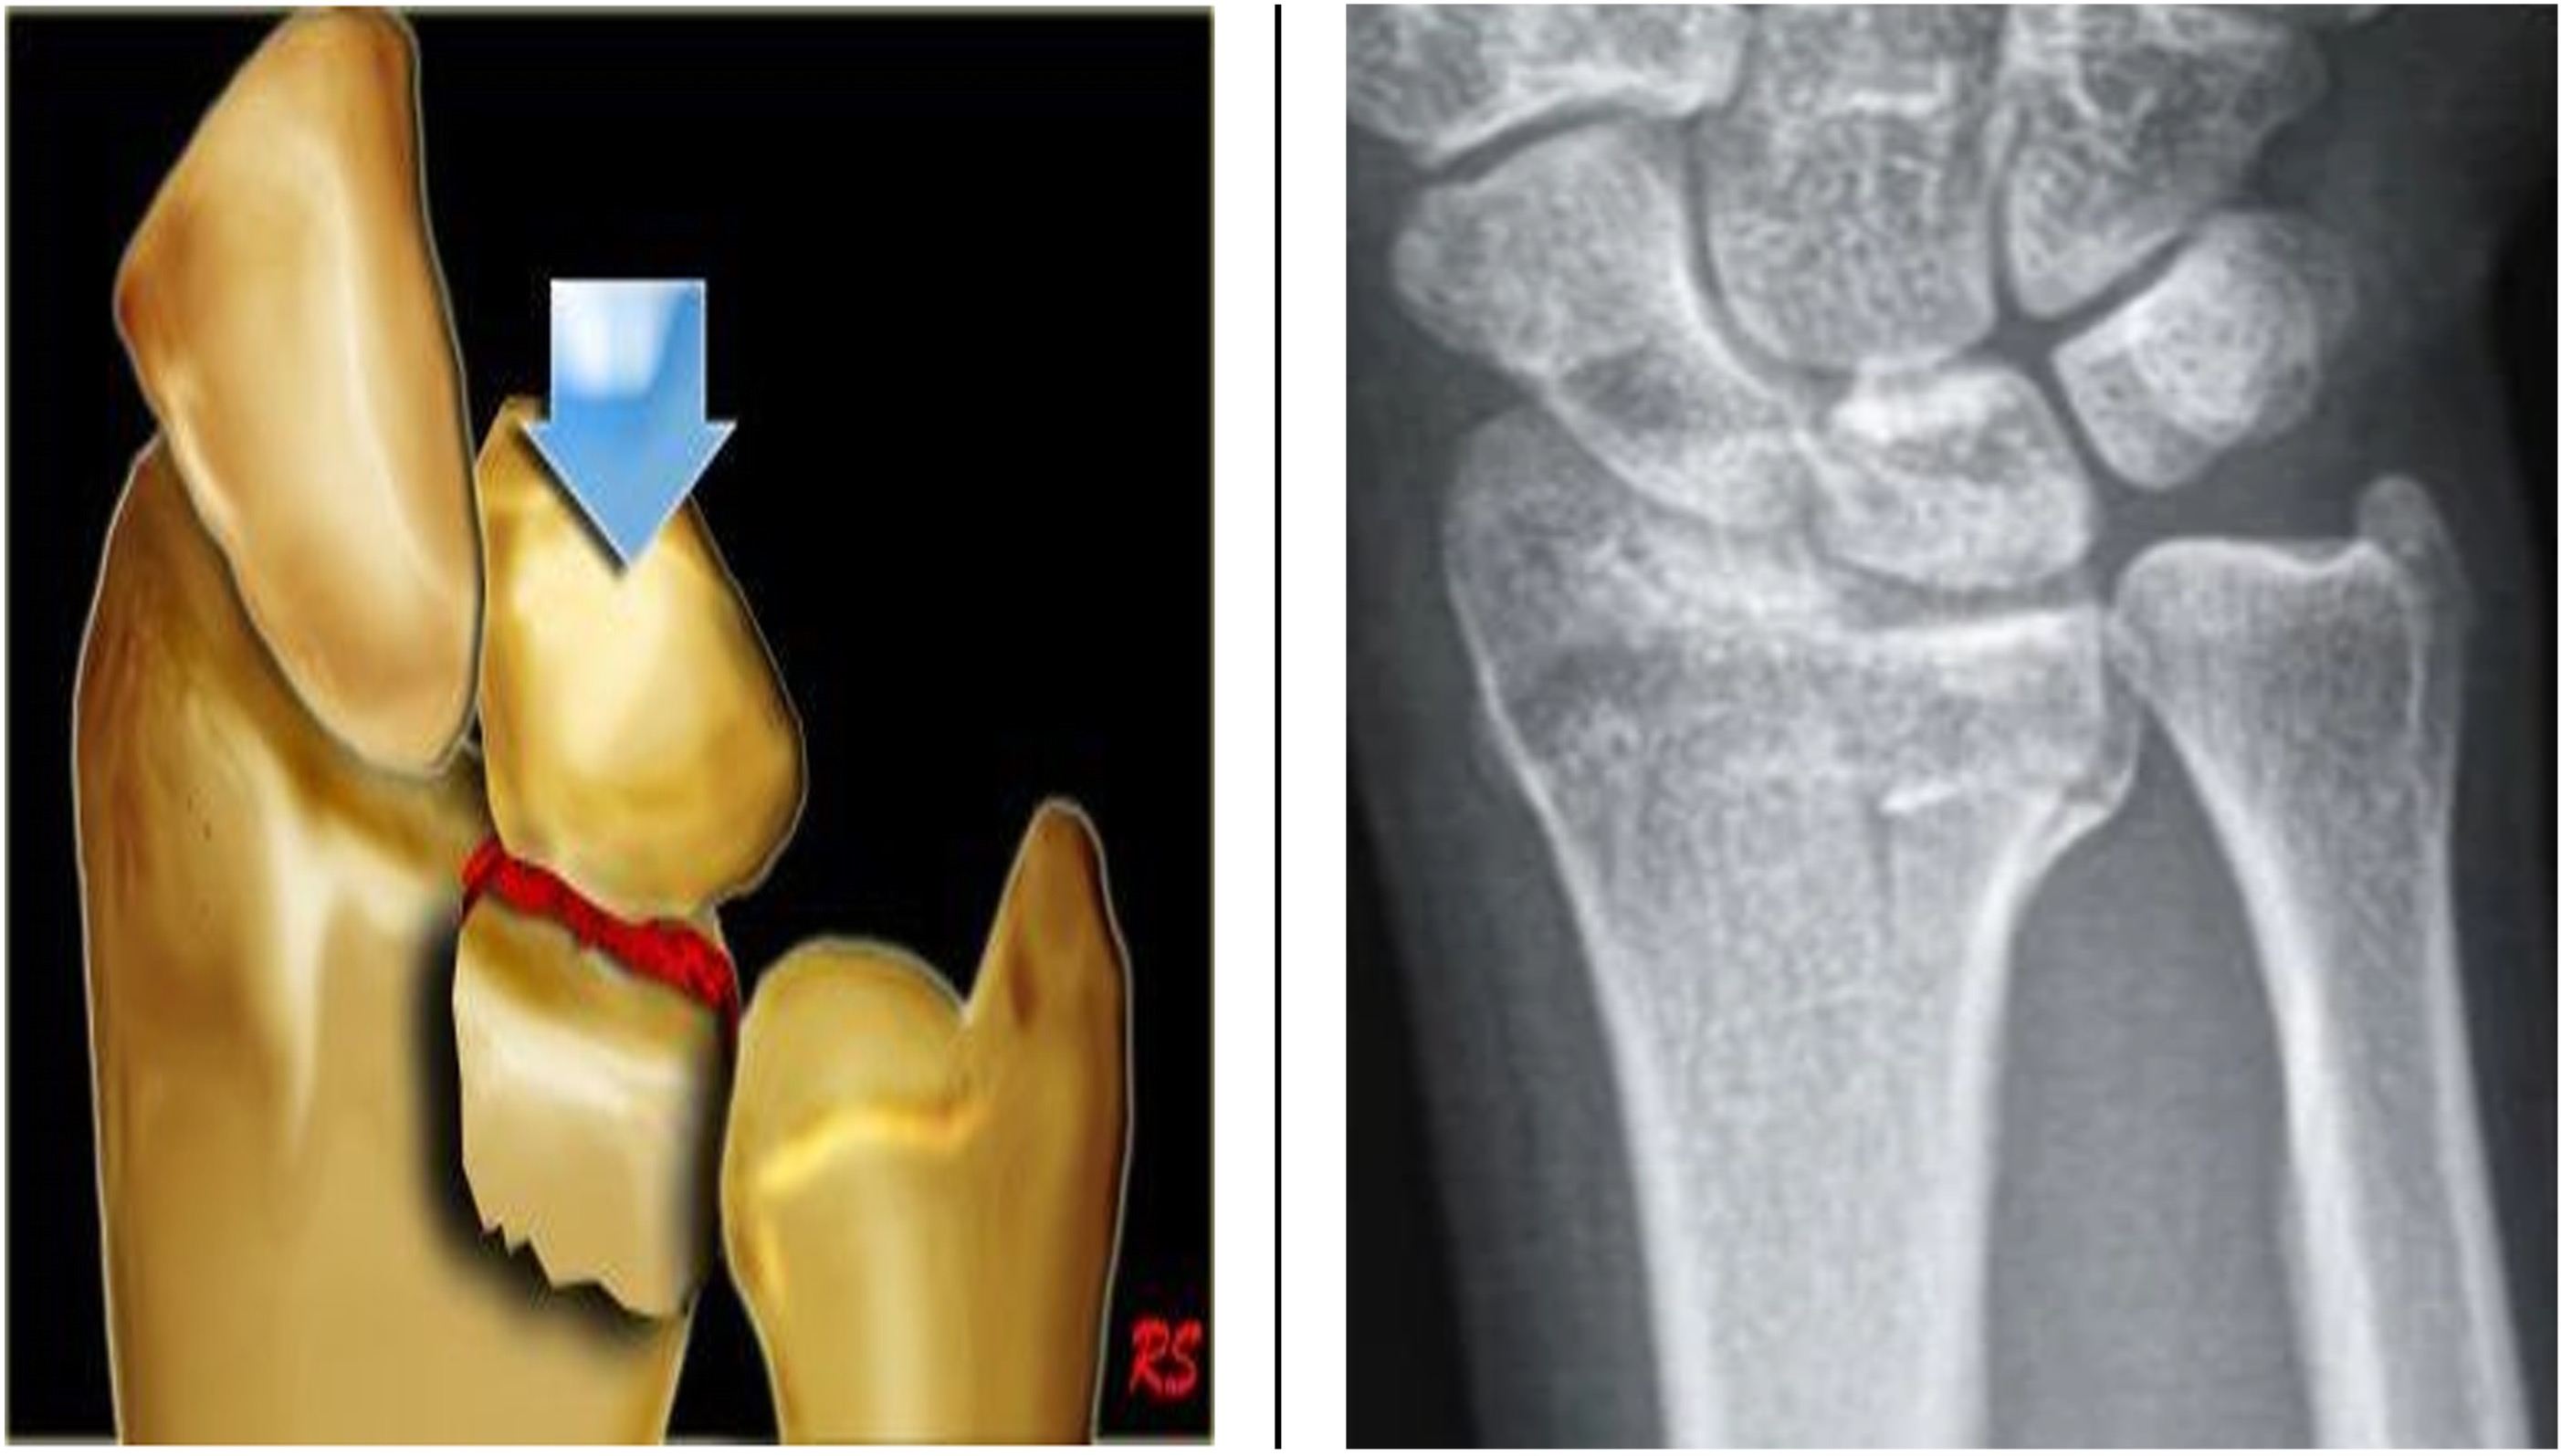

Diagnose

Ofte etter fall på utstrakt arm. Bakre luksasjon er vanligst. Kombinert med bruddskade i 30-40 % av tilfellene. Vanligst er brudd i proc. coronoideus, caput radii, capitellum humeri eller olecranon. Albueluksasjon kan medføre kar- og nerveskade. Undersøk og journalfør perifer sirkulasjon, motorikk og sensibilitet før og etter reponering som anført i albueluksasjonsfrasen i DIPS: N.Ulnaris (f.eks sprikekraft og sensibilitet 5.finger), n. medianus (O-tegn og sensibilitet volart 1.-3. finger) og n. radialis (dorsalfleksjon håndledd og sensibilitet dorsalt 1. webspace).

Behandling